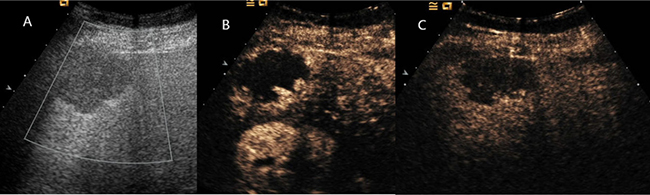

Figure 2: Hepatic hemangioma showed peripheral nodular enhancement in all vascular phases. (A) Ultrasound revealed a hypoechoic mass under right liver capsular. (B) and (C) CEUS showed peripheral nodular enhancement throughout the whole vascular period.

Figure 3: Hepatic hemangioma showed peripheral circular enhancement in all vascular phases. (A) Ultrasound revealed a hypoechoic mass in the right liver. (B) and (C) CEUS showed peripheral circular enhancement throughout the whole vascular period.